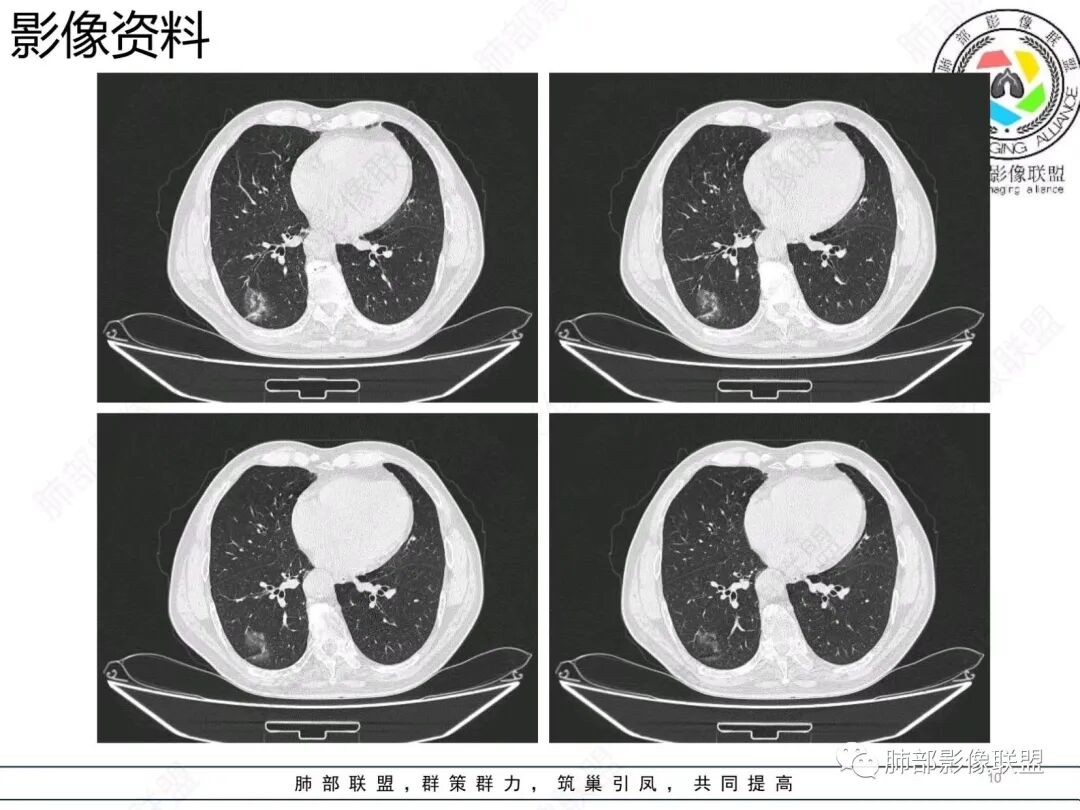

老年男性,右肺下叶混合磨玻璃密度结节,可见血管弯征,首先考虑肺腺癌。

右肺下叶背段不规则结节,边界欠清,可见少许晕征,另见胸膜凹陷征及血管弯,考虑腺癌,鉴别隐球菌。

右肺下早不规则结节,周围少许磨玻璃晕,胸膜有牵拉凹陷,虽然部分边界平直,但血管受牵拉弯曲,首先还是考虑肿瘤,腺癌

右肺下叶背段斑片影,边缘平直、局部膨隆,可见磨玻璃密度影,界清,胸膜牵拉,良恶性需要进一步鉴别,倾向隐球,鉴别粘液腺癌。

老年男性,右肺下叶胸膜下结节,边缘见清晰磨玻璃密度影及少许索条,支气管进入后截断,周围血管弯,考虑腺癌,鉴别隐球菌

右肺下叶胸膜下混合密度结节,分叶、毛刺,磨玻璃边界尚清晰,血管集束,支气管进入阻断,考虑腺癌

右肺下叶背段胸膜下肿块,边缘不规则,分叶,毛刺,有磨玻璃,边界清,近肺门侧见血管聚集,支气管进入后闭塞,右肺下叶肺静脉牵拉扭曲。诊断,支持腺癌

老年患者,无呼吸道相关症状,肺部影像学表现:胸膜下占位,有结节融合趋势,内有低密度灶。考虑隐球菌,鉴别腺癌。

胸膜下结节,与胸膜平行,多结节融合,边缘模糊,直边征,考虑炎性肉芽肿,隐球,腺癌

右肺下叶背段实性结节,边缘分叶,较平直,长轴平行胸膜,胸膜增厚,考虑炎性假瘤,隐球菌,鉴别腺癌。

混合性磨玻璃结节,边界清晰,血管打弯,考虑腺癌,鉴别炎性肉芽肿病变。

老年男性,体检发现,无症状,右肺下叶背段肿块影,边缘清楚,无卫星灶,棘状突起,毛刺征,血管集支束,空泡征,考虑恶性肿瘤。

老年男性,体检发现。右肺下叶混合磨玻璃结节,渗漏征,短毛刺,血管集支束,空泡,考虑腺癌。

老年男性右肺下叶靠近胸膜一不规则混合密度影,周围有渗出,内见支气管扩张,考虑炎性病变隐球鉴别腺癌

老年男性 右肺下叶胸膜下见一团状实性病灶+边缘磨玻璃,边缘形态不规则,,局部有平直,长轴平行于胸膜面,整体收缩力偏弱,邻近胸膜面轻度增厚,纵隔窗显示病灶内可见支气管充气,考虑炎性肉芽肿,隐球菌可能,鉴别黏液腺癌。

右肺下叶实行病灶,边缘部分有边界清晰的磨玻璃影,实变明显层面,可见平直。考虑腺癌

右下肺近胸膜病变,周围可见磨玻璃影,界限无法判断清楚?模糊?。考虑右下肺占位:真菌感染?腺癌?淋巴瘤?

右肺下叶胸膜下结节,边界清楚毛玻璃,有分叶、毛刺、血管集束及胸膜增厚,考虑肉芽肿性病变,鉴别于腺癌

右肺下叶实性病灶,局部平直,考虑炎性病变,隐球菌可能

胸膜下结节,长轴与胸膜平行,边缘模糊,直边征胸膜凹陷牵拉不明显,考虑炎性肉芽肿,隐?鉴别腺癌。

右肺下叶后基底段胸膜下斑块影,边缘清楚,有平直和膨隆特点,周围清楚GGO,较模糊(似清非清,邻近见多发纯GGO结节,以肺腺泡分布,主体病灶与胸膜平行,收缩力弱,边缘见支气管充气征,首诊断炎性肉芽肿,抗炎治疗和查下隐球荚膜抗原两方面进行,另取旧片对比,与粘液腺Ca鉴别,最后经皮肺穿刺病理诊断!

上面这些征象存在炎性病变可能,我先考虑炎性病变——隐球,这样的血管弯在肺隐球菌病里也出现过。腺癌尤其是粘液腺癌也不敢排除。建议完善血隐球菌荚膜抗原、经皮肺穿刺活检等检查。

结节型粘液腺癌,具有血管弯,支气管截断,磨玻璃边界清楚等恶性征象,同时磨玻璃内部较糊,似清非清,不符合普通腺癌附壁生长特点,更像局限的粘液成分。收缩力不强,胸膜局部微积液,内部小空洞(考虑局部粘液排除形成),所以考虑结节型粘液腺癌。